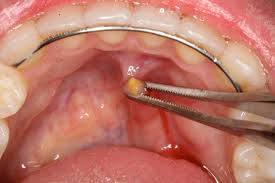

مقالة علمية للتدريسي م.م.محمد فارس بعنوان Salivary gland stone

A salivary gland stone also called salivary duct stone is a calcified structure that may form inside a salivary gland or duct. It can block the flow of saliva into the mouth.<br />The majority of stones affect the submandibular glands located at the floor of the mouth. Less commonly, the stones affect the parotid glands, located on the inside of the cheeks, or the sublingual glands, which are under the tongue. Many people with the condition have multiple stones.<br /><br />Causes and Symptoms<br />Salivary stones form when chemicals in the saliva accumulate in the duct or gland. They mostly contain calcium. The exact cause is not known. But factors contributing to less saliva production and/or thickened saliva may be risk factors for salivary stones. These factors include: dehydration, poor eating, and use of certain medications including some antihistamines, blood pressure drugs, psychiatric drugs, and bladder control drugs. Trauma to the salivary glands may also raise the risk for salivary stones.<br />The stones cause no symptoms as they form, but if they reach a size that blocks the duct, saliva backs up into the gland, causing pain and swelling. You may feel the pain off and on, and it may get progressively worse. Inflammation and infection within the affected gland may follow.<br />Diagnosis and Treatments<br />If you have symptoms of a salivary gland stone, your doctor will first check for stones with a physical exam. Sometimes tests may also be ordered, such as X-ray, CT scan, or ultrasound.<br />If a stone is detected, the goal of treatment is to remove it. For small stones, stimulating saliva flow by sucking on a lemon or sour candies may cause the stone to pass spontaneously. In other cases where stones are small, the doctor or dentist may massage or push the stone out of the duct.<br />For larger, harder-to-remove stones, doctors usually make a small incision in the mouth to remove the stone.<br />More and more, doctors are using a newer and less invasive technique called sialendoscopy to remove salivary gland stones. Developed and used successfully in Europe for a decade, sialendoscopy uses tiny lighted scopes, inserted into the gland's opening in the mouth, to visualize the salivary duct system and locate the stone. Then, using micro instruments, the surgeon can remove the stone to relieve the blockage. The procedure is performed under local or light general anesthesia, which allows the patient to go home the same day.<br />